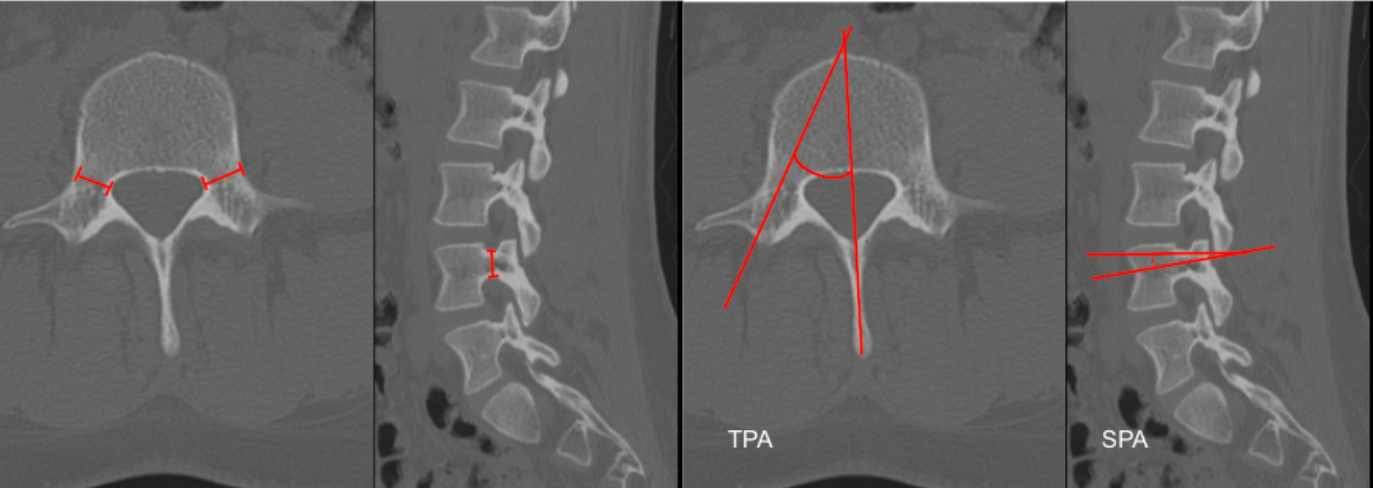

Lumbar pedicle morphometry quantifies the size and orientation of the pedicles and is essential for safe pedicle screw placement. Measurements include:

• Pedicle width (transverse diameter)

• Pedicle height (sagittal diameter)

• Transverse pedicle angle (TPA) – determines medial–lateral screw trajectory

• Sagittal pedicle angle (SPA) – determines cephalocaudal screw trajectory

A. Pedicle Width (Transverse Diameter) – Axial CT

• Select the axial slice at the pedicle mid-body level.

• Identify the medial and lateral cortices of the pedicle.

• Measure the minimum transverse distance (mm) between cortices.

B. Pedicle Height (Sagittal Diameter) – Sagittal CT

• On parasagittal CT, identify the pedicle.

• Measure the minimum superior–inferior distance (mm) between pedicle cortices.

C. Transverse Pedicle Angle – Axial CT

• Draw a line through the pedicle axis.

• Draw a reference line along the posterior vertebral body wall.

• Measure the angle between these lines — this is the medial angulation angle.

D. Sagittal Pedicle Angle – Sagittal CT

• Draw a line along the pedicle axis.

• Draw a horizontal reference line through the posterior vertebral body wall.

• Measure the angle — this is the cephalocaudal trajectory angle.